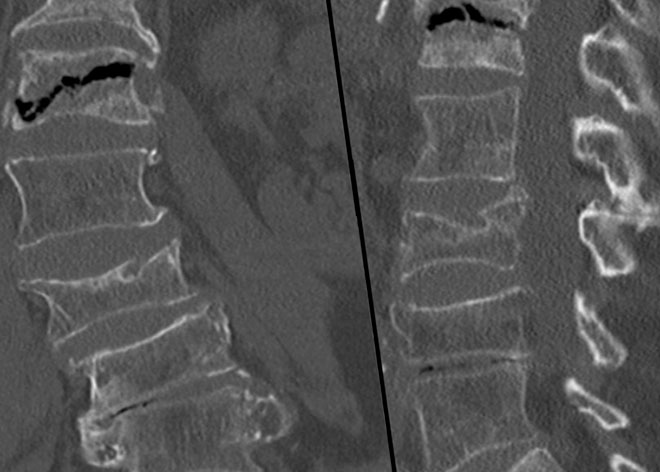

На рентгенограмме при третьей стадии отмечается сплющивание поражённого позвонка. При этом сплющивание может происходить как равномерно, так и по краям – больше справа или слева. Со временем позвонок может уменьшиться до трети своего размера.

Что касается структурных изменений, то они не обнаруживаются. При этом поражение сразу нескольких позвонков при травматическом спондилите – это большая редкость.

Диагноз может быть поставлен только на основании сочетания клинической картины и рентгенологического исследования. К тому же, только на основании этого исследования можно планировать тот или иной способ лечения. Если же в диагностике есть затруднения, то можно порекомендовать пациенту сделать КТ или МРТ исследования. Посмотреть результаты этих процедур при болезни Кюммеля можно на фото.